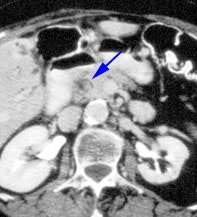

|

Choledocholithiasis: The hepatobiliary exam demonstrated prompt uptake of the radiotracer with no excretion. The findings were consistent with acute common bile duct obstruction. Despite this diagnosis, a CT scan was performed to exclude a pancreatic neoplasm. A stone can be seen in the distal common bile duct on the CT exam (blue arrow). Click CT to enlarge. |